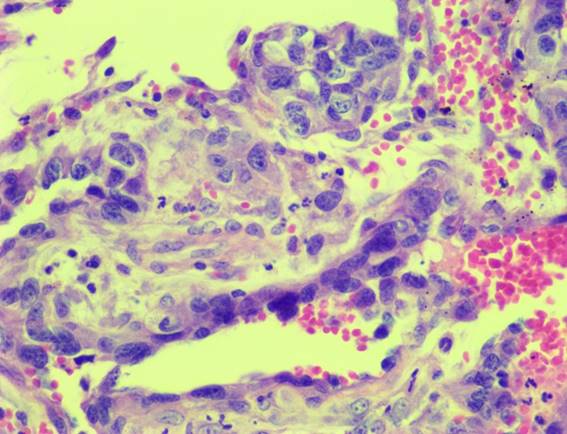

En esa consulta se repitió la pericardiocentesis, obteniendo 150 ml de un líquido serosanguinolento, que no coaguló incluso hasta haber transcurrido más de una hora. Se remitió una muestra al laboratorio Vetin (Montevideo) para estudio citológico. El informe citológico dio un resultado compatible con hemangiosarcoma, la celularidad encontrada fue de células del tipo endotelial prominentes de gran tamaño con anisocitosis, vacuolas intracitoplasmáticas, alterada relación núcleo citoplasma y presencia de mitosis (figura 2).

Figura 2: Imagen microscòpica a 200x del frotis obtenido de la pericardiocentesis y teñido con May Grunwald Giemsa. Se observan células endoteliales prominentes con alterada relación núcleo citoplasma, con abundantes vacuolas intracitoplasmáticas. Línea densa referencia de 25 µm

Se remitió muestra de aurícula derecha para su estudio histopatológico y se concluyó el diagnóstico de hemangiosarcoma con tinción de Hematoxilina-Eosina (figura 14).

Figura 14: Aumento 40x. Tinción con Hematoxilina y Eosina de una sección de aurícula derecha. Se observa una neoformación no encapsulada, no bien delimitada de un crecimiento tendiendo a formar espacios vasculares de células elongadas con citoplasma eosinófilo con los límites celulares poco nítidos. El núcleo es oval grande vesicular con la presencia de nucléolos prominentes en algunas células e hipercrómatico en otras. En algunas pequeñas áreas estas células están formando pequeños capilares con sangre en su luz. Hay extensas áreas de necrosis.